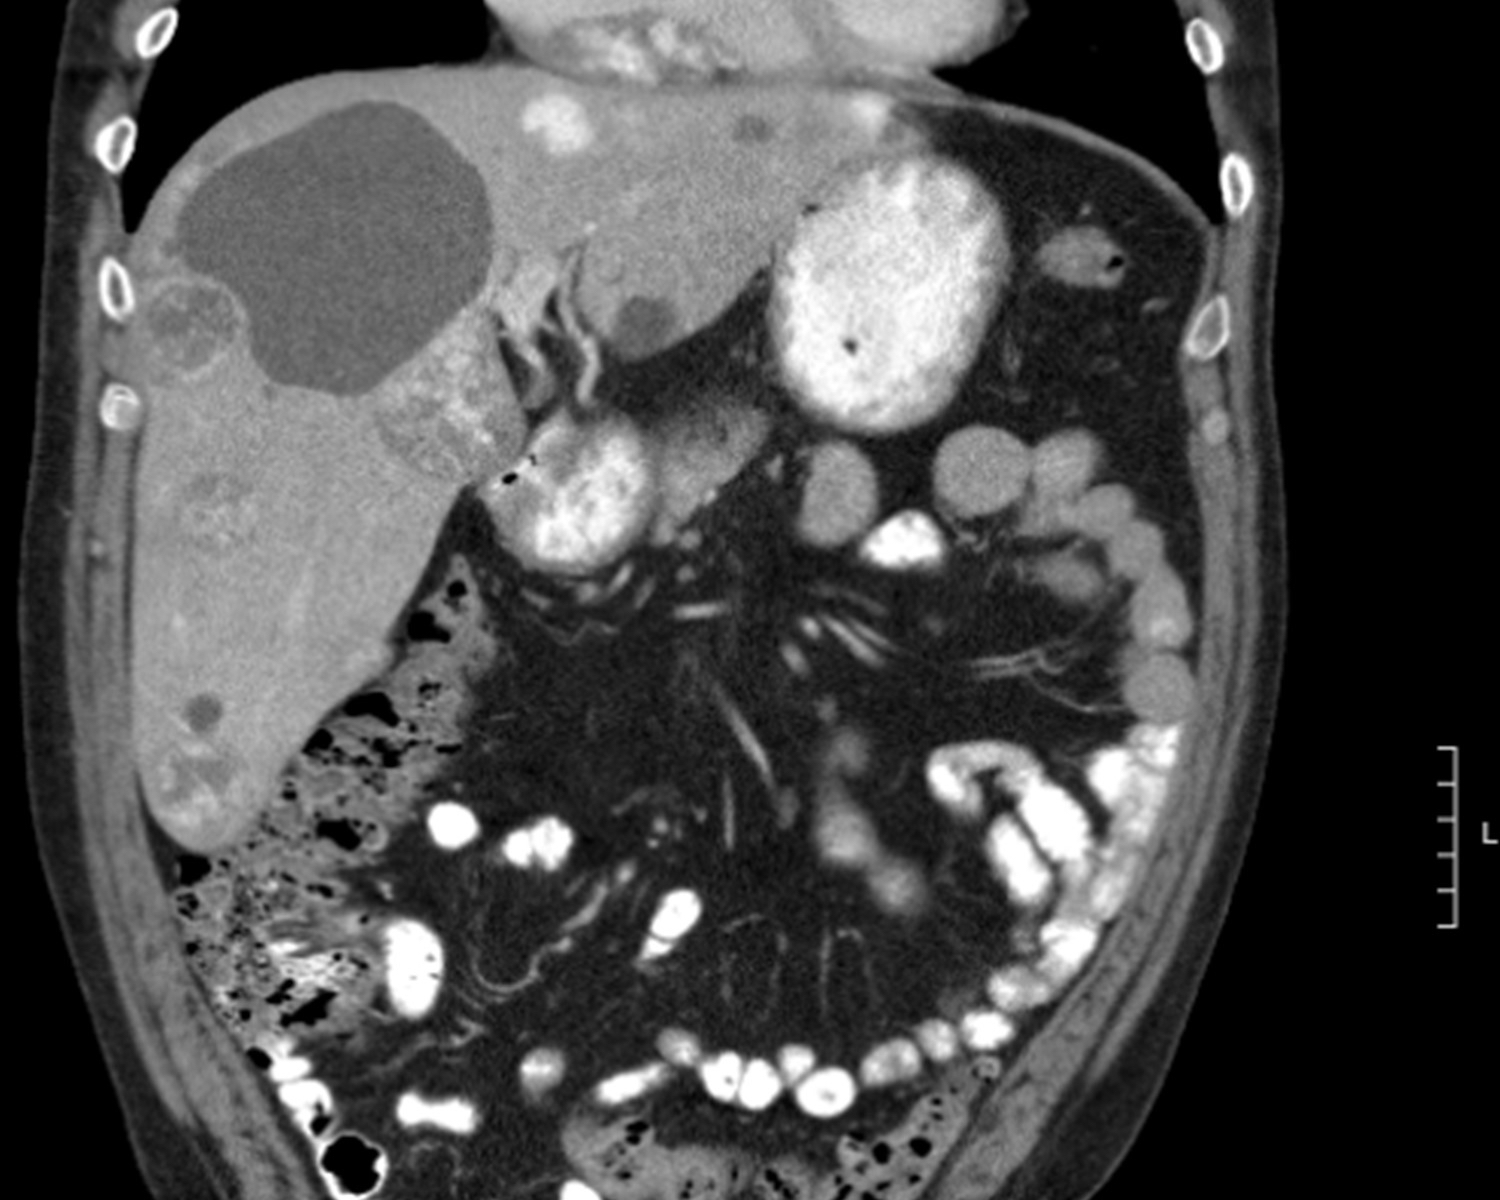

Radiology description

- Ultrasound: peripheral echogenicity and central hypoechoic appearance; color Doppler study shows hypervascularity of the tumor (World J Gastroenterol 2017;23:2443)

- Noncontrast computed tomography (CT): hypoattenuating masses with focal hyperattenuation, suggestive of hemorrhage; hyperattenuating linear meshwork in Thorotrast cases

- Contrast CT: heterogeneous irregular enhancement consistent with necrosis and fibrosis; disorganized, patchy enhancement in later phases (Br J Radiol 2017;90:20170039)

- Magnetic resonance imaging (MRI) T1 / T2: heterogeneous areas of high signal, indicating a mix of tumor tissue and hemorrhage (Radiopaedia: Hepatic Angiosarcoma [Accessed 29 October 2024])